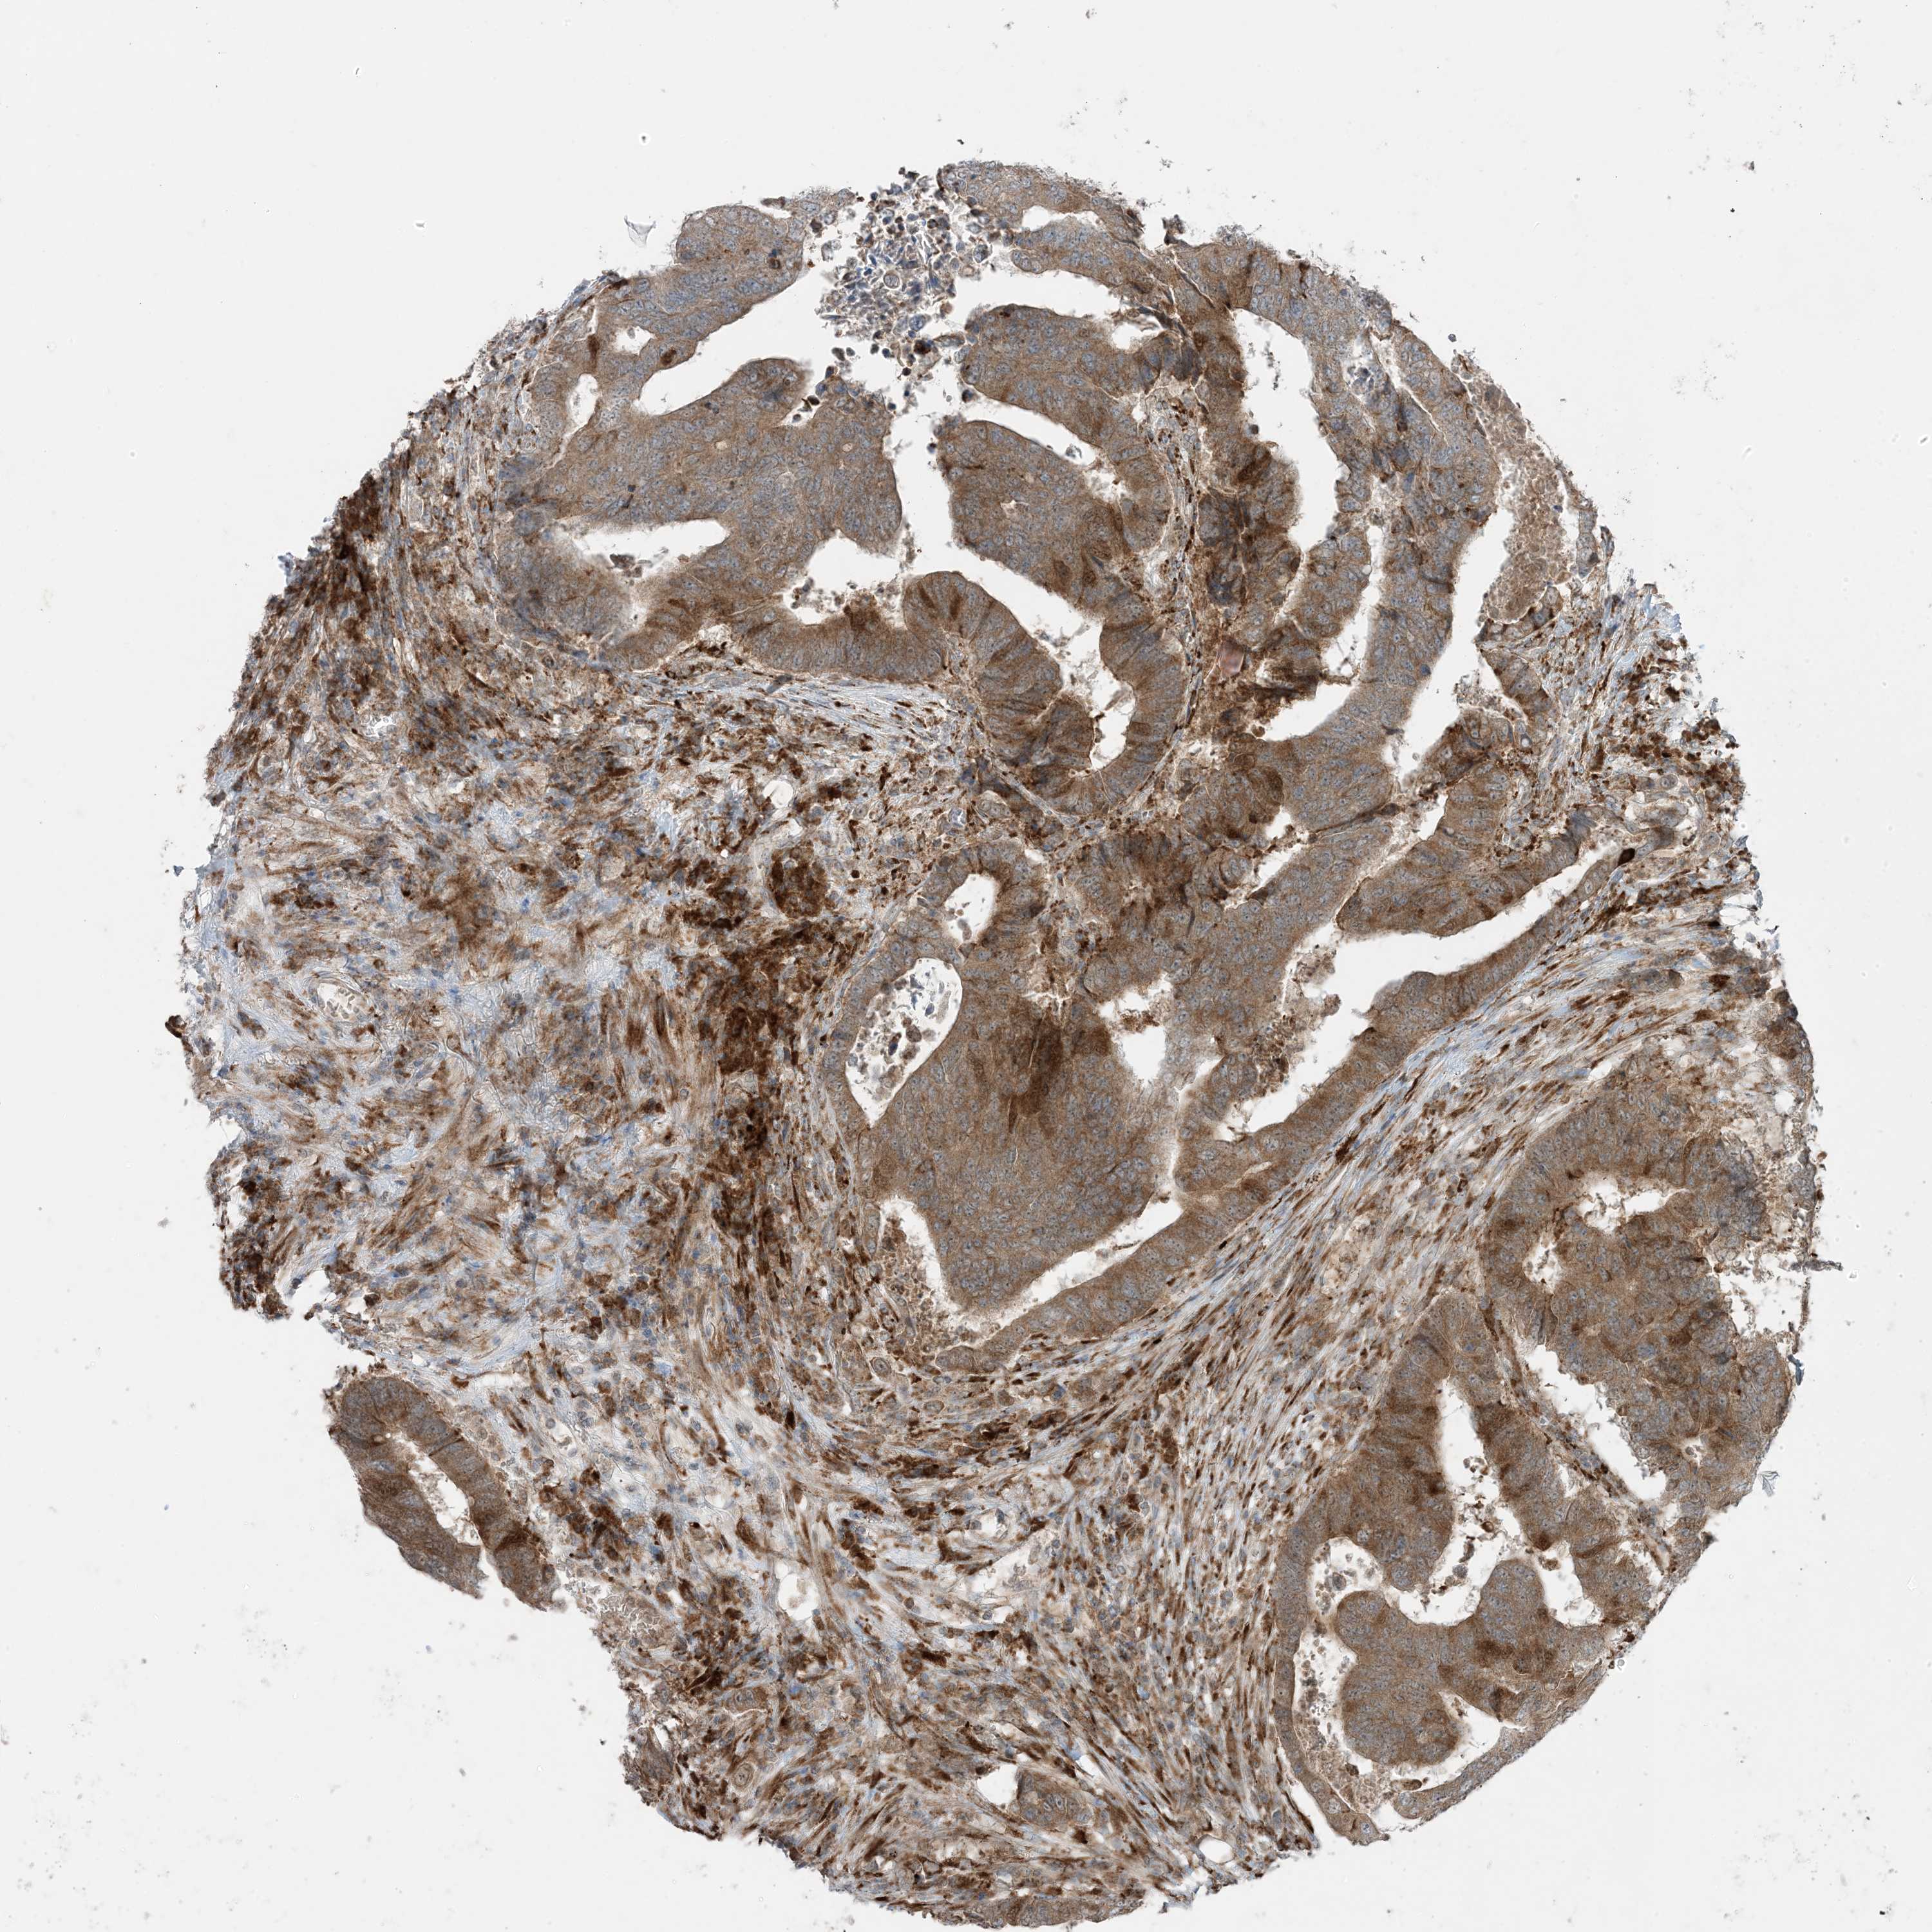

Colorectal cancer

Rectum adenocarcinoma